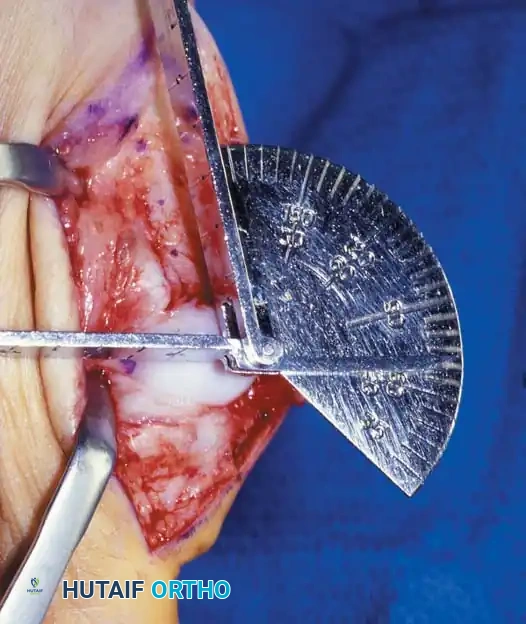

Inadequate vascularity or sensibility should be investigated thoroughly before bunion surgery is considered. In addition, the position of the articular surface of the metatarsal head in relation to the longitudinal axis of the fi rst metatarsal should be determined (Fig. 78-8). Standard preoperative radiographs should include standing dorsoplantar and lateral views, a nonstanding lateral oblique view, and axial sesamoid views (Fig. 78-9). The hallux valgus angle and the fi rst-second intermetatarsal angle should fi rst be drawn on the standing dorsoplantar view by bisecting the shafts of the bones (Fig. 78-10), with an awareness of the normal ranges. These angles are most frequently cited as guidelines for treatment decisions, but Donnelly et al. reported that interobserver measurements of the hallux valgus angle varied by approximately 6 degrees and of the intermetatarsal angle by 4 degrees. They cautioned that potential errors in measurement should be considered when these parameters are used to make treatment decisions. The hallux valgus interphalangeus angle and any evidence of degenerative arthritic changes at the fi rst metatarsophalangeal or metatarsocuneiform joints should be documented. Oddities may be present and, if overlooked, may compromise a technically well-done procedure. Mann emphasized that the presence of an os inter-

Fig. 78-8 A, Determination of position of articular surface of metatarsal head in relation to longitudinal axis of fi rst metatarsal. B, Measurement of distal metatarsal articular angle at time of surgery. Markings are at medial and lateral margins of articular surface of fi rst metatarsal head and longitudinal axis of fi rst metatarsal shaft. metatarseum between the bases of the fi rst and second metatarsals might preclude the effectiveness of a soft-tissue procedure alone to provide suffi cient correction of the increased intermetatarsal angle. Likewise, accessory sesamoids and prominent ungual tuberosities at the interphalangeal joint contribute to a painful callus at the tibial side of this joint. An os tibialis externum frequently is associated with excessive hallux valgus interphalangeus. Varus of the fi rst metatarsal might be a signifi cant part of the overall deformity of the foot even with an intermetatarsal angle of less than 10 degrees. Metatarsus varus with a relatively small hallux valgus angle (15 to 20 degrees) may produce signifi cant deformity even though the angles are not excessive. The usefulness of computer-assisted compared with manual measurement of the intermetatarsal angle, hallux valgus angle, and distal metatarsal articular angle is still uncertain. Both methods have closer interobserver and intraobserver correlation in measurement of the intermetatarsal angle and hallux valgus angle than in measurement of the distal metatarsal articular angle. The reliability of either method has such a wide range (5 degrees), however, that measurements of these angles, although useful as a guide, do not provide a completely reliable indication of the magnitude of deformity. Condon et al. suggested that the reliability of the intermetatarsal angle can be improved by careful technique and by making the measurements at least twice and averaging them. Schneider et al. reported two methods of determining angular measurements based on distinctly different reference points: (1) a longitudinal axis of the fi rst metatarsal using middiaphyseal reference points, and (2) a center-head technique using a center head (center of the articular surface) and center base